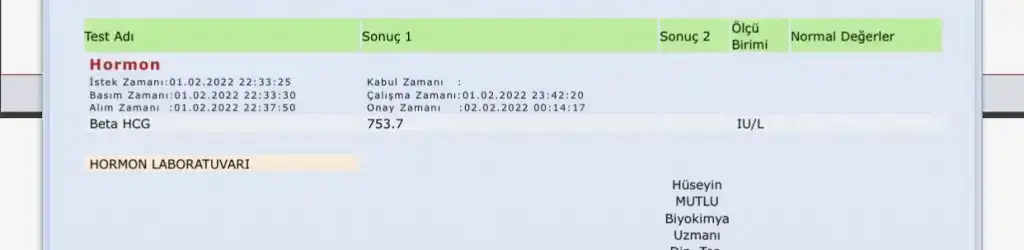

Merhaba hanımlar 1 Şubatta adet olmam gerekiyordu olmayınca akşamı test yaptım çift çizgi çıktı hemen kan verdim beta hcg 753.7 çıktı dün ( 3 şubat) bir damla kan geldi korktum bugün doktorumla görüştüm erken olduğu için ultrasonda gözükmez tekrar beta hcg ye baktır 1500 civarina geldiyse sıkıntı yok demektir dedi bende tekrar kan verdim bu sefer de değerim 2567 çıktı doktor yarın gel ultrasonda bakalım dedi şimdi merak ediyorum kısa sürede bu kadar yükselmesi normal mi yoksa ikiz gebelik olabilir mi ve kaç haftalık oluyor son adetimin ilk günü 2 Ocak bu arada ilk gebeliğim şimdiden teşekkürler

Alakası yok onla benim düşükte o degedi tek di ultrason da bile bu değer çoğul dedi tek çıktı normal bu kadar yüksek olması iki günde bir iki katı katlıyor ultrason da gözüküyor üsten bu değerle git bak buraya da yazMerhaba hanımlar 1 Şubatta adet olmam gerekiyordu olmayınca akşamı test yaptım çift çizgi çıktı hemen kan verdim beta hcg 753.7 çıktı dün ( 3 şubat) bir damla kan geldi korktum bugün doktorumla görüştüm erken olduğu için ultrasonda gözükmez tekrar beta hcg ye baktır 1500 civarina geldiyse sıkıntı yok demektir dedi bende tekrar kan verdim bu sefer de değerim 2567 çıktı doktor yarın gel ultrasonda bakalım dedi şimdi merak ediyorum kısa sürede bu kadar yükselmesi normal mi yoksa ikiz gebelik olabilir mi ve kaç haftalık oluyor son adetimin ilk günü 2 Ocak bu arada ilk gebeliğim şimdiden teşekkürler

Ablamın daha yüksekti tek gebelik di beeta ya gire bilmez kimse usg de belli olur yarine zaten değer yükselir 3000 olur ordan gözükür beta 30 60 90 diye gdiip te ikiz olan da okudum ben 20 25 30 diye gidipte olan da ikiz gördüm beta ile alakası yok beta isterse 800.00 bin olsun tek de olabilir hakkınızda hayırlısı olsun inşallahMerhaba hanımlar 1 Şubatta adet olmam gerekiyordu olmayınca akşamı test yaptım çift çizgi çıktı hemen kan verdim beta hcg 753.7 çıktı dün ( 3 şubat) bir damla kan geldi korktum bugün doktorumla görüştüm erken olduğu için ultrasonda gözükmez tekrar beta hcg ye baktır 1500 civarina geldiyse sıkıntı yok demektir dedi bende tekrar kan verdim bu sefer de değerim 2567 çıktı doktor yarın gel ultrasonda bakalım dedi şimdi merak ediyorum kısa sürede bu kadar yükselmesi normal mi yoksa ikiz gebelik olabilir mi ve kaç haftalık oluyor son adetimin ilk günü 2 Ocak bu arada ilk gebeliğim şimdiden teşekkürler